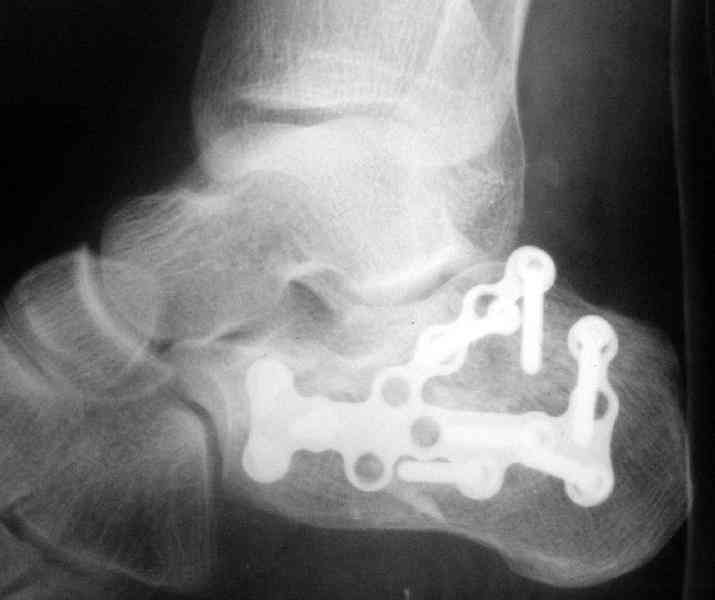

Открытый и закрытый способы лечения.